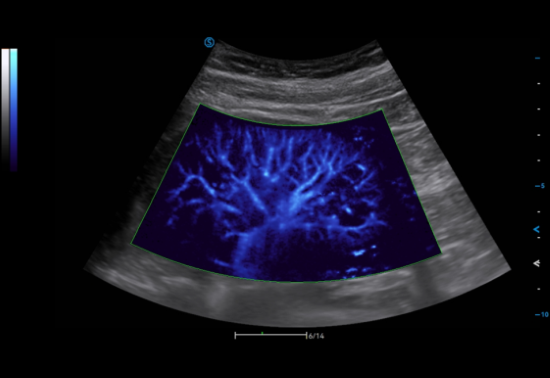

Micro Flow sensitively detects micro blood flow signals to precisely reflect the blood flow perfusion status in organs.